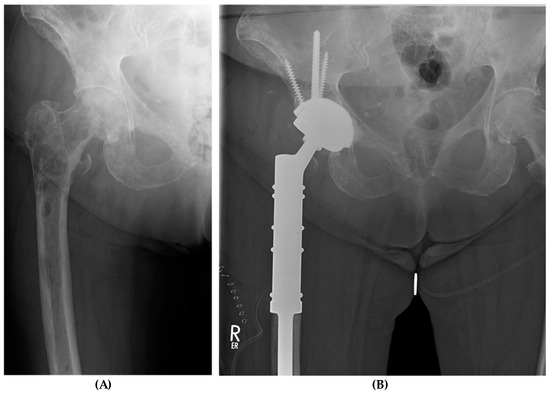

| Patient Number | Age (Years) | Primary Tumor | ASA a | Mobilization Preoperative | Mobilization at Latest FU b | Follow-Up (Months) | Patient Survival | Implant Survival (Yes/No) |

|---|---|---|---|---|---|---|---|---|

| #1 | 70 | Multiple myeloma | 3 | Two crutches | Unaided | 24 | DOD c | yes |

| #2 | 59 | Prostate cancer | 4 | Wheelchair | Cane | 7 | DOD c | yes |

| #3 | 76 | Breast cancer | 3 | Wheelchair | Two crutches | 6 | DOD c | yes |

| #4 | 73 | Non-Hodgkin lymphoma | 4 | Wheelchair | Cane | 35 | AWD d | yes |

| #5 | 82 | Breast cancer | 3 | Wheelchair | Two crutches | 6 | DOD c | yes |

| #6 | 74 | Breast cancer | 3 | Wheelchair | Unaided | 19 | AWD d | yes |

| #7 | 69 | Renal cell carcinoma | 3 | Two crutches | Two crutches | 6 | DOD c | yes |

| #8 | 56 | Bronchial cancer | 4 | Wheelchair | Two crutches | 10 | AWD d | yes |

| #9 | 60 | Bronchial cancer | 4 | Wheelchair | Walking frame | 8 | AWD d | yes |

| #10 | 79 | Prostate cancer | 3 | Two crutches | Cane | 10 | AWD d | yes |

| #11 | 66 | Breast cancer | 3 | Two crutches | Cane | 8 | AWD d | yes |

| #12 | 75 | Breast cancer | 2 | Wheelchair | Cane | 36 | AWD d | yes |